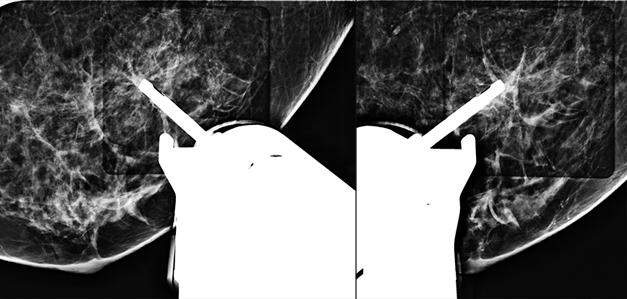

Simulated 3D Breast Biopsy Procedure

Introductory Video: 3D Breast Biopsy Procedure with Eviva® biopsy device